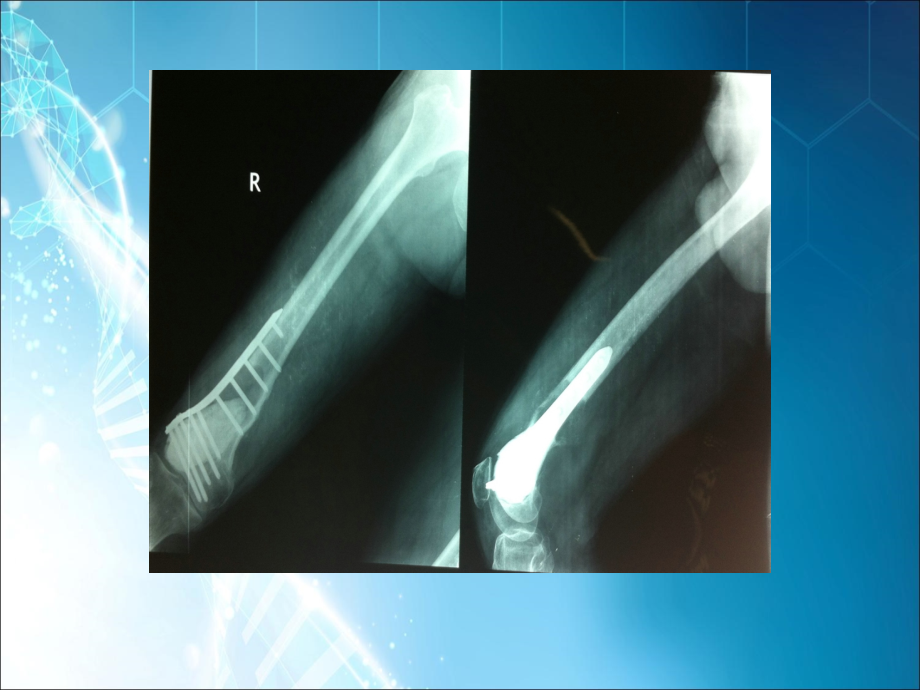

病 例 讨 论,武警医院关节外科,魏海清、陆金荣,基本情况,患者范,XX,,男性,,48,岁,浙江平湖市人,因“右股骨下段骨肿瘤术后,1,年”入院。,基本情况,患者于,1,年前出现右大腿下段酸痛不适,无夜间痛,无畏寒、发热,、,无盗汗,与天气变化无明显关系,就诊于嘉兴市,XX,医院,诊断为右股骨下端骨肿瘤(骨巨细胞瘤),并行右股骨下段肿瘤刮除内固定,+,骨水泥填塞术,手术顺利。现患者术后,1,年,感右大腿下段酸痛不适,来我院复查,X,线片(,2011-03-07,)提示:右股骨下端骨肿瘤术后观,内固定在位,股骨下端见高密度影填充,部分见斑片状骨质缺损,骨皮质破损,考虑肿瘤复发。建议住院手术,故门诊拟“右股骨下段骨肿瘤(骨巨细胞瘤)术后”收入我科。,基本情况,专科查体:脊柱生理弧度存在,右大腿无肿胀,股四头肌轻度萎缩,右大腿下段外侧可见一约,14CM,陈旧性手术疤痕,愈合良好,局部皮温不高,无红肿,右膝伸屈活动范围:,0-65,度,过伸过屈试验阴性,双踝关节及足趾活动正常,左下肢及双上肢未见明显异常及功能障碍。,辅助检查,全身,ECT,:右股骨下段及右侧膝关节处放射性异常高度浓聚。查全胸片、血常规、血凝分析、生化常规、乙肝三系、三抗未见明显手术禁忌。,手术情况,2011-03-13,在硬膜外麻醉下行右股骨肿瘤段切除,+,人工全膝关节置换(肿瘤假体)术,术中见整个关节滑膜充血、变性增厚、粘连、纤维增生,有大量淡黄色液体,股骨髁上可见肿瘤,骨质破坏,皮质骨变薄,其内有较多坏死组织,钢板螺钉在位,顺利取下肿瘤及内固定(距肿瘤近端约,8cm,处,包括股骨远端),术中快速切片病理报告为,:,骨巨细包瘤。,假体由美国史塞克公司提供,术后,1,周,术后,1,周,术后,2,周,术后,3,周,2015-05-25,复查结果,讨论?,此类患者若术前确诊为骨巨细胞瘤,首次手术:,内固定,VS,置换,讨论?,骨巨细胞瘤在,1940,年首次被,Jaffe,发现,可能起始于骨髓内间叶组织。骨巨细胞瘤具有较强侵袭性,对骨质的溶蚀破坏作用大,极少数有反应性新骨生成及自愈倾向,可穿过骨皮质形成软组织包块,,刮除术后复发率高,,少数可出现局部恶性变或肺转移(即所谓良性转移)。,骨巨细胞瘤为低度恶性或潜在恶性的肿瘤。,讨论?,1.,局部切除骨巨细胞瘤切除后,若对功能影响不大,可完全切除,如腓骨上端、尺骨下端等。,2.,刮除加辅助治疗用骨水泥填充肿瘤内切除所剩的空腔时,产生的热量可预防复发,即骨水泥的致热反应造成局部发热,使残存肿瘤组织坏死,却不损伤正常组织,避免并发症出现。,3.,切除或截肢骨巨细胞瘤如为恶性,范围较大,有软组织浸润或术后复发,应根据具体情况考虑局部切除或截肢。有的切除肿瘤后,关节失去作用(如股骨颈),可考虑应用人工关节或关节融合术。,4.,放射治疗,我们的经验,该类患者若用骨水泥填充,应充分刮除,不留残余,以防复发;,对范围较大者,有软组织浸润者,我们更倾向于直接瘤段切除,+,限制性肿瘤假体置换。,